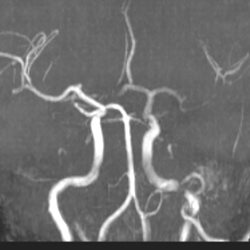

Arterial Case 09A - Hyperacute Stroke

42 year old male with right sided numbness and neck pain; history of seizures and hypertension.